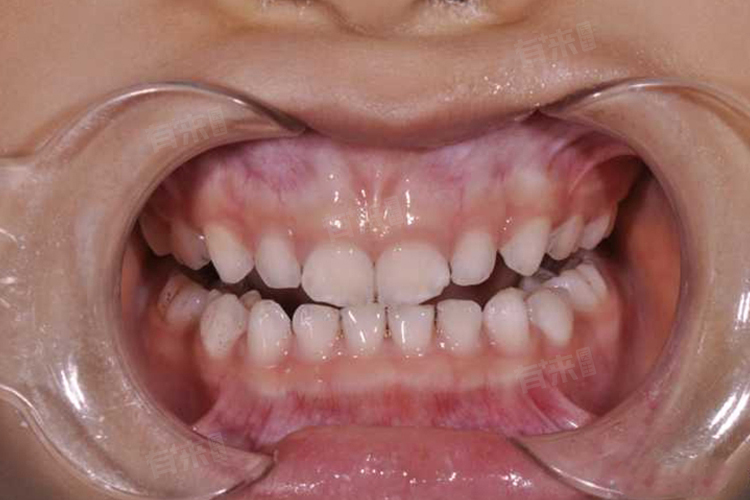

小孩牙齿发白钙化,这一现象可能由多种原因引起,主要包括牙齿脱矿、牙釉质发育不全以及氟斑牙等。

1、牙齿脱矿:牙齿脱矿是导致牙齿发白钙化的一个重要原因。当牙齿表面的牙釉质受到酸性物质的侵蚀,如长期摄入过多甜食或碳酸饮料,细菌在牙面上代谢蔗糖产酸,会导致牙釉质表面的钙磷脱落,形成白色或微黄的斑点。这些斑点不仅影响美观,还可能进一步导致牙釉质脱落,使牙齿表面变得凹凸不平。

2、牙釉质发育不全:牙釉质发育不全也是造成牙齿发白的一个原因。牙釉质是牙齿最外层的硬组织,具有保护牙齿的作用。然而,如果儿童在生长发育过程中,由于全身营养失调(特别是钙、磷、维生素等营养素的缺乏)、乳牙根尖周炎症感染、全身性疾病(如水痘、猩红热等)或乳牙外伤等因素,都可能导致牙釉质发育不全。发育不全的牙釉质在颜色和质地上都可能与正常牙釉质有所不同,表现为发白或钙化不足的现象。

3、氟斑牙:氟斑牙是牙釉质在发育期摄入了过多的氟导致的牙体组织疾病。当儿童长期饮用氟含量超标的水或生活在空气污染且含氟毒素的环境中,以及使用含氟牙膏不当等,都可能引发氟斑牙。氟斑牙的表现为同一时间萌出的牙齿牙釉质上出现白垩色到褐色程度不等的斑块,可伴有釉质缺损。这些斑块不仅影响美观,还可能对牙齿的咀嚼功能和健康产生不良影响。